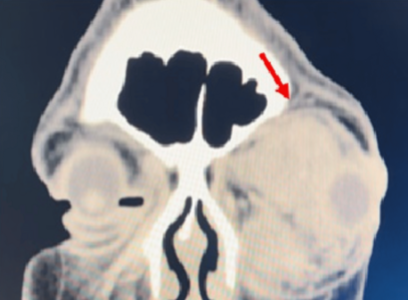

|  | | |  | | “11년 방치해 실명”…‘이 병’ 3개월 안에 발견하면 완치할 수 있어 | | 눈 안쪽 혈관에 생긴 종양이 시신경을 눌러 실명으로 이어진 사례가 나왔다. 반면, 같은 병이라도 증상이 나타난 지 3개월 안에 병원을 찾은 환자는 시력을 되찾았다.11일(현지시간) 말레이시아 페락주 에포 국립병원 의료진은 국제 의학… |